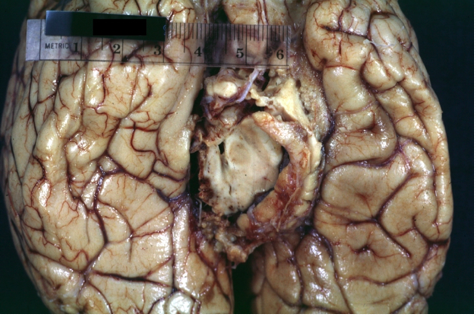

What does this image show?

Tonsillar herniation